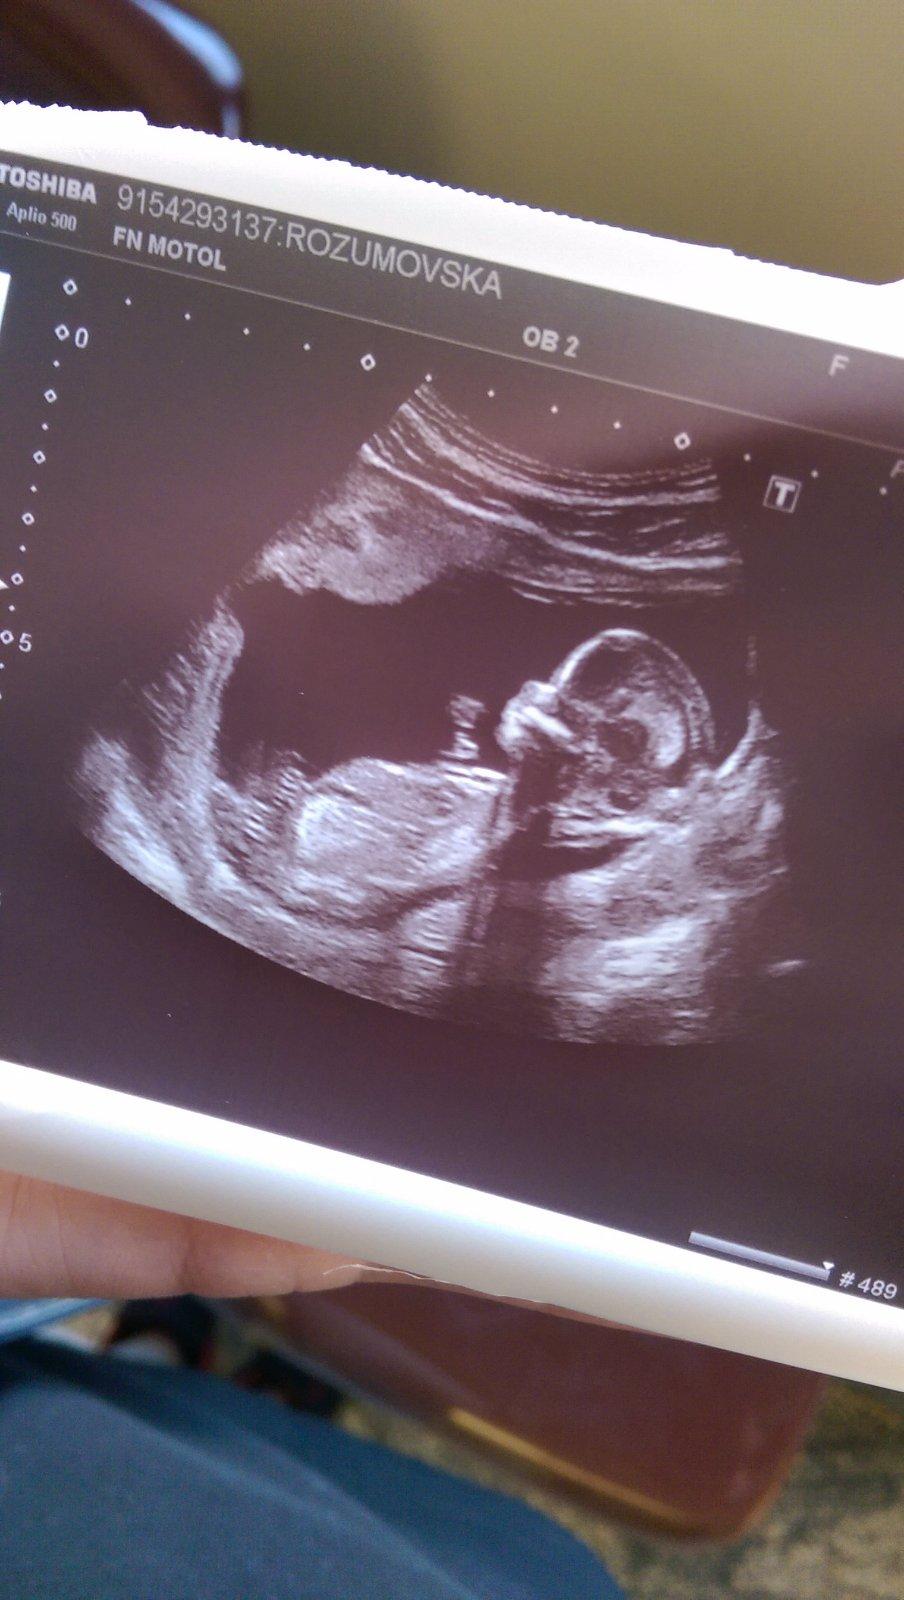

Ahoj holky 🙂 tak mam po prvotrimestralnim screeningu 🙂 cvrcek je zdravy, ma pet prstu na kazde rucicce,,srdicko krasne bije, hlavicka v poradku. Jen jsme starsi 🙂 termin se posunul na 11.1.2018 a jsme 14+0tt ❤